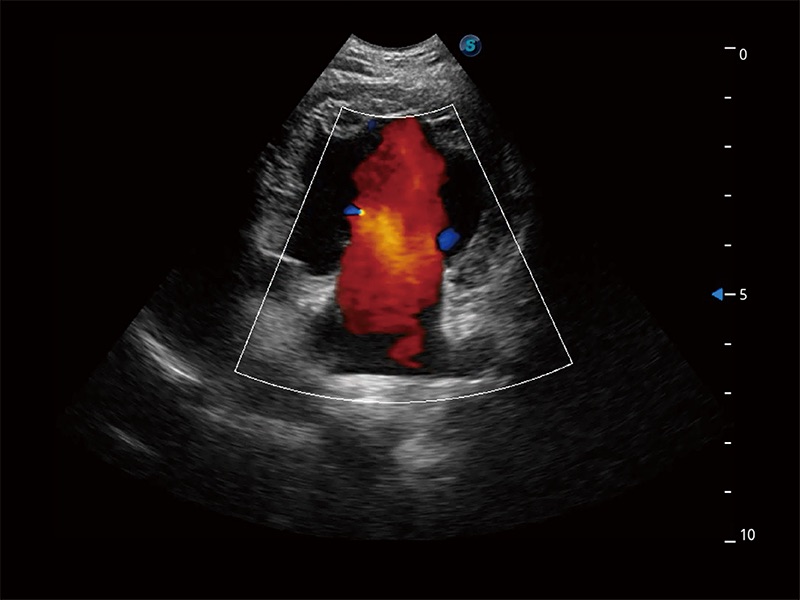

极大提升超低速微细血流的检出能力,同时更精准地滤除软组织和超声信号,为兽用医生提供以往无法通过常规血流获得的疾病诊断信息。